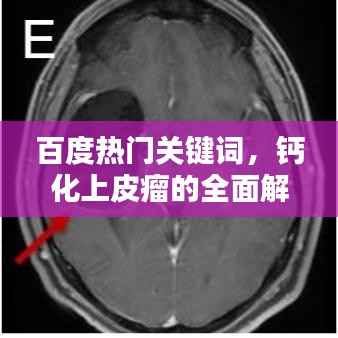

当我们谈论“钙化上皮瘤”这一医学名词时,许多人可能会感到陌生和困惑,本文将通过“百度一下”的方式,带您全面了解钙化上皮瘤,包括其定义、成因、症状、诊断以及治疗方法。

钙化上皮瘤,也被称为皮肤钙化瘤,是一种皮肤良性肿瘤,这种肿瘤主要由过度增生的上皮细胞和钙盐沉积组成,大多数情况下,它们是良性的,不会对身体造成严重影响,它们可能会在皮肤表面形成硬质结节,有时会引发疼痛或不适。

钙化上皮瘤的症状主要包括皮肤表面的硬质结节,可能伴有疼痛或瘙痒,这些结节可能单独出现,也可能成簇出现,它们可能在不同年龄阶段出现,但通常在成年后才会被发现。

如果您怀疑自己可能患有钙化上皮瘤,最好寻求专业医生的帮助,医生会通过观察皮肤结节的外观、触摸其质地以及询问您的病史来进行初步诊断,在某些情况下,可能需要进行皮肤活检以确诊。